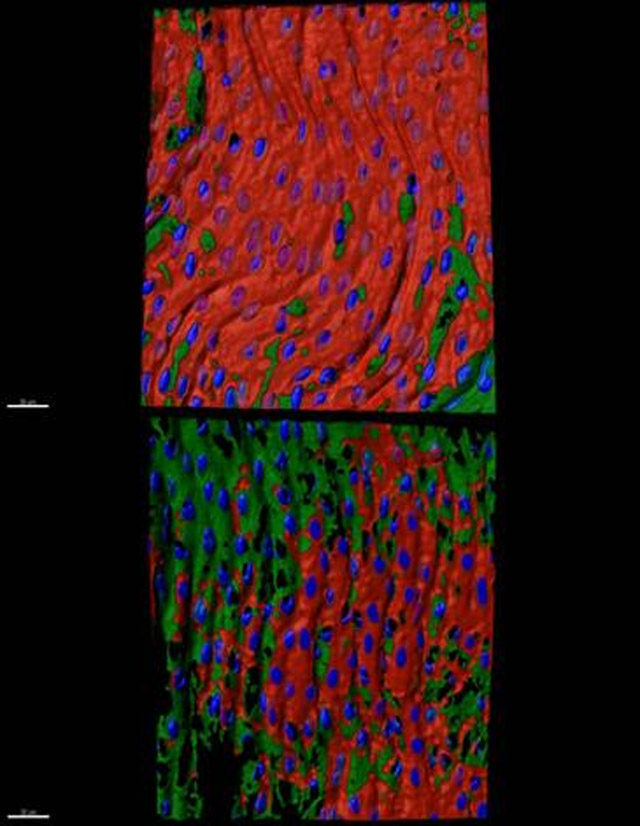

Detección de ILK (rojo), células endoteliales (verde), en una arteria humana sana (arriba) y una arteria humana aterosclerótica (abajo)